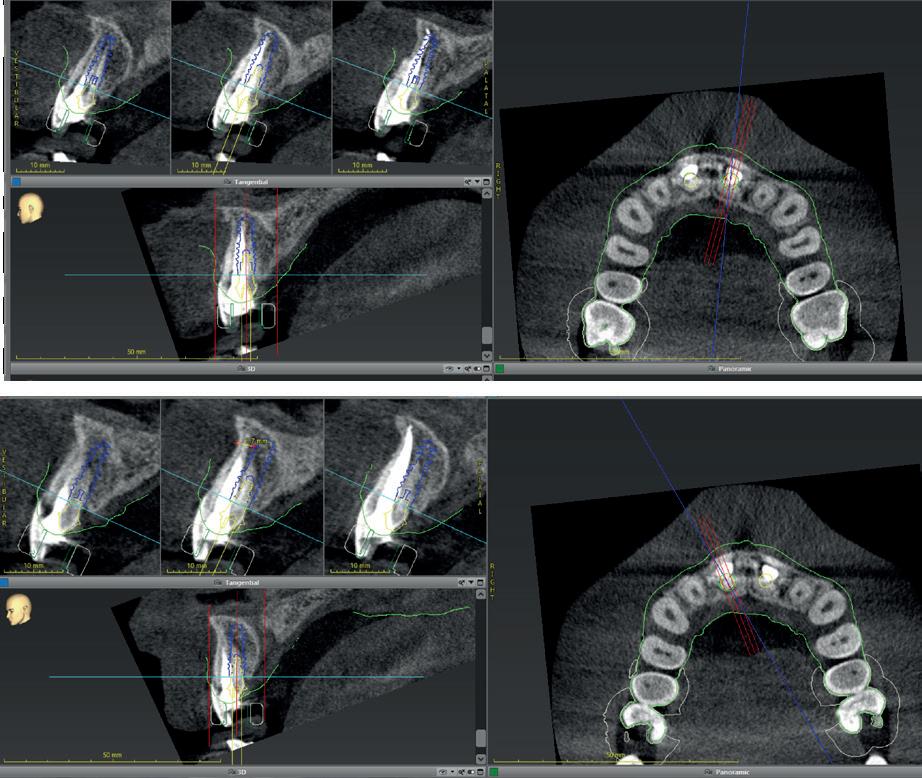

Na vier maanden wordt er een CBCT gemaakt om het botvolume te kunnen beoordelen en een digitale planning te kunnen maken voor het plaatsen van het implantaat. Tevens wordt de stabiliteit van de botpieken op het buurelementen bekeken (foto 15 en 16).

Tijdens het verwijderen van het membraan is het botvolume klinisch waarneembaar en blijkt dat er voldoende bot is om het implantaat te kunnen plaat-

sen. Tijdens deze procedure wordt er ook een free gingival graft van het palatum gehaald. Deze wordt buccaal aangebracht van de 22 en 23 om zo de recessie zoveel mogelijk te bedekken en de papil tussen de 22 en 23 van meer volume te voorzien.

De flap en graft worden met poly-propelene 6.0 hechtingen gefixeerd. De tijdelijke reconstructie wordt herplaatst (foto 17-20).

In afbeeldingen 5a-d is de implantaatkroon 37 te zien, twee jaar na plaatsing. Op de röntgenfoto is herstel van zowel corticaal als spongieus bot te zien. (De CB-CT was vervaardigd in verband met implantologische indicatie in het naastliggende gebied).